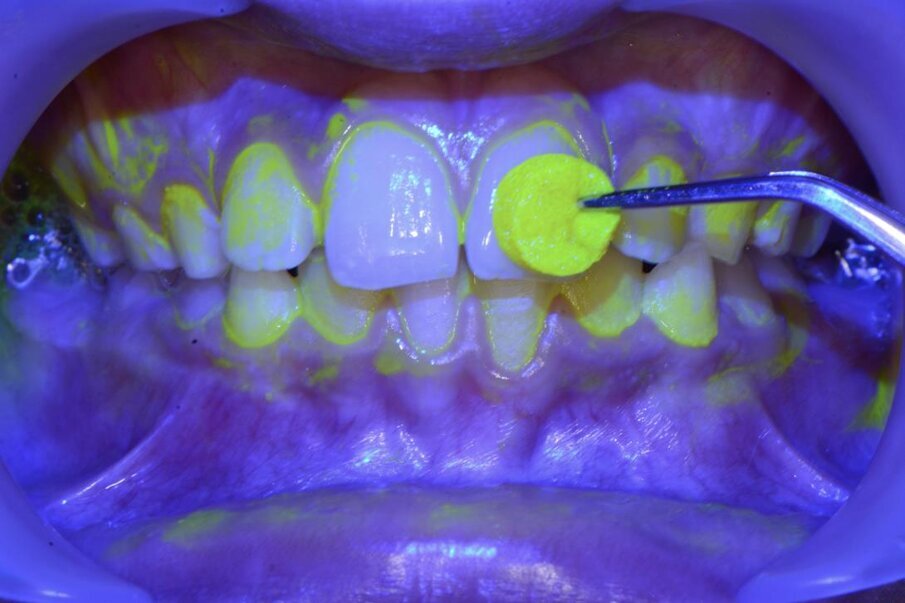

La scelta di una seduta o sgabello non ergonomica diventa una scelta importante, considerando il timing frequente di utilizzo. Usare i divaricatori durante l’esecuzione odontoiatrica (Fig. 3), eviterà il disagio dell’affaticamento all’assistente odontoiatrica poiché eliminerà le tensioni alle articolazioni della mano durante il divaricamento con specchietto, con l’obbiettivo di facilitare la visuale dell’operatore assistito. L’utilizzo degli ingranditori ad esempio (Fig. 4), aiutano l’operatore a mantenere una giusta postura alla poltrona odontoiatrica e migliorano la visibilità del sito clinico, diminuendo i tempi di lavoro e soprattutto migliorando l’efficacia della prestazione. Un rivelatore di placca potrà permettere di visualizzare la topografia del biofilm batterico per permettere un deplaquing efficace (Fig. 5), che non sprechi polvere di glicina o di bicarbonato, contenendo il timing dell’operatività di airpolishing e limitando l’inquinamento dell’ambiente. A livello internazionale esiste un brand che lavora su strumenti ideati da addetti al settore che risultano essere altamente ergonomici poiché basati sull’esperienza della pratica clinica di professionisti.